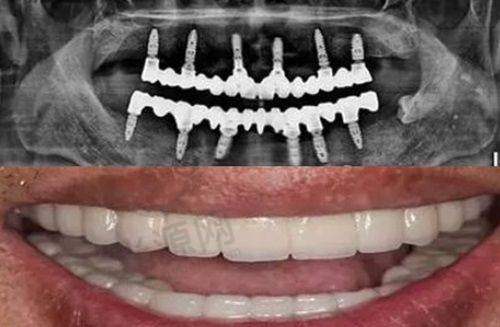

种植技术:拥有数字化口腔种植技术,如即拔即种种植牙、即刻负重种植牙、半口种植牙、全口种植牙等。其中即刻负重技术,对于牙槽骨条件好的患者,上午种牙,下午戴临时冠,吃饭社交两不误;数字化导板种植技术,术前3D建模,避开神经血管,误差控制在0.2mm内,对怕疼的患者非常友好。